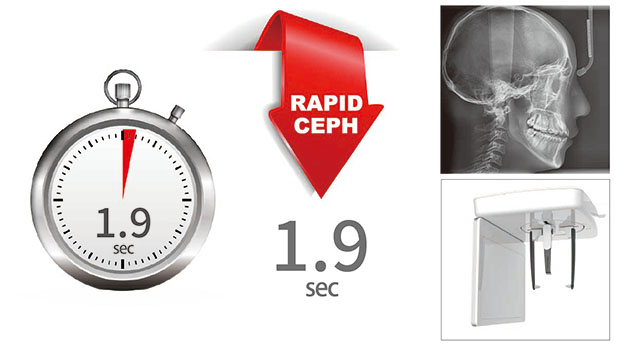

使用更少的扫描时间有效减少运动伪影。拍摄头颅侧位仅需1.9秒,加快了工作流程。减少辐射剂量的同时提高了影像质量。

提供多样的头颅侧位摄影模式。

| 标准头颅侧位 | 1.9sec | |